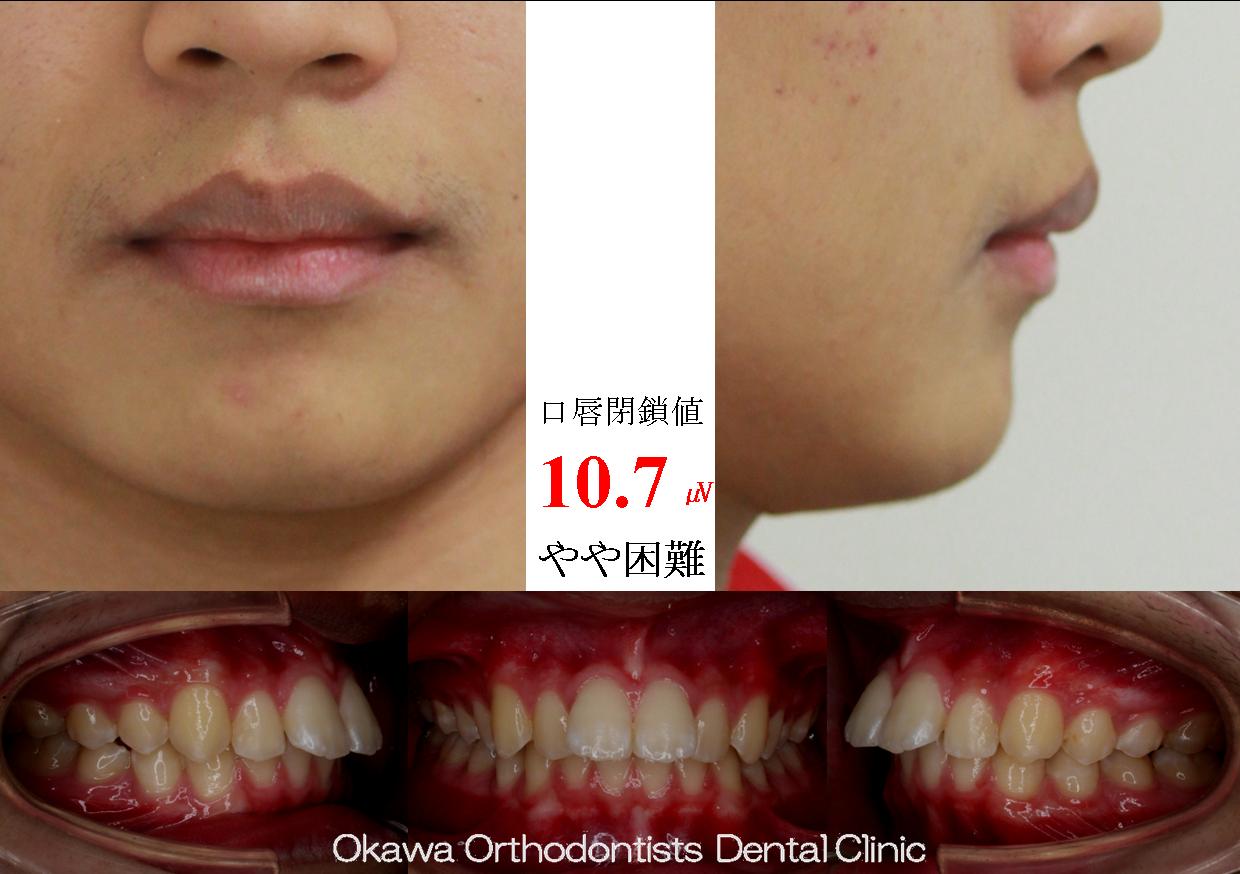

早割 万博 BK06039.jpg 医学一般